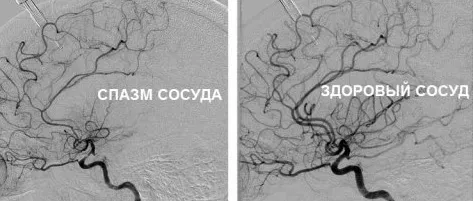

• По гипертоническому типу. Наблюдается при повышенном артериальном давлении, когда сосуды мозга в состоянии спазма, просвет сосуда уменьшен из-за сокращения мышечной стенки артерии.

• По гипотоническому типу. Возникает у людей, склонных к низкому артериальному давлению. Стенки сосудов расслаблены и их просвет увеличен.